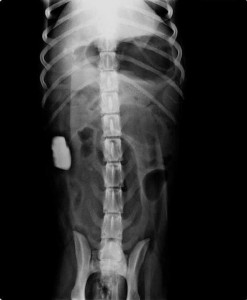

calculs a la radio

présence de nombreux calculs vésicaux dans la vessie de ce chien